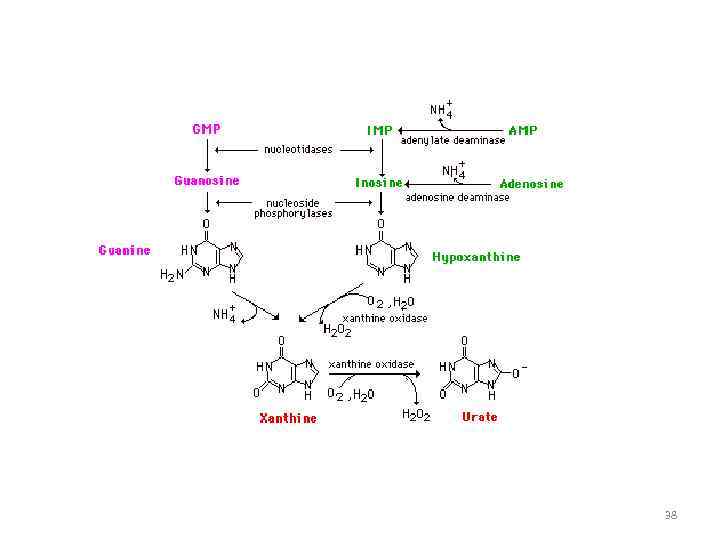

37

38

Активаторы ксантиноксидоредуктазы • Рибоксин (инозин) • Молибден • Медь • Железо • Рибофлавин-5 -фосфат 39